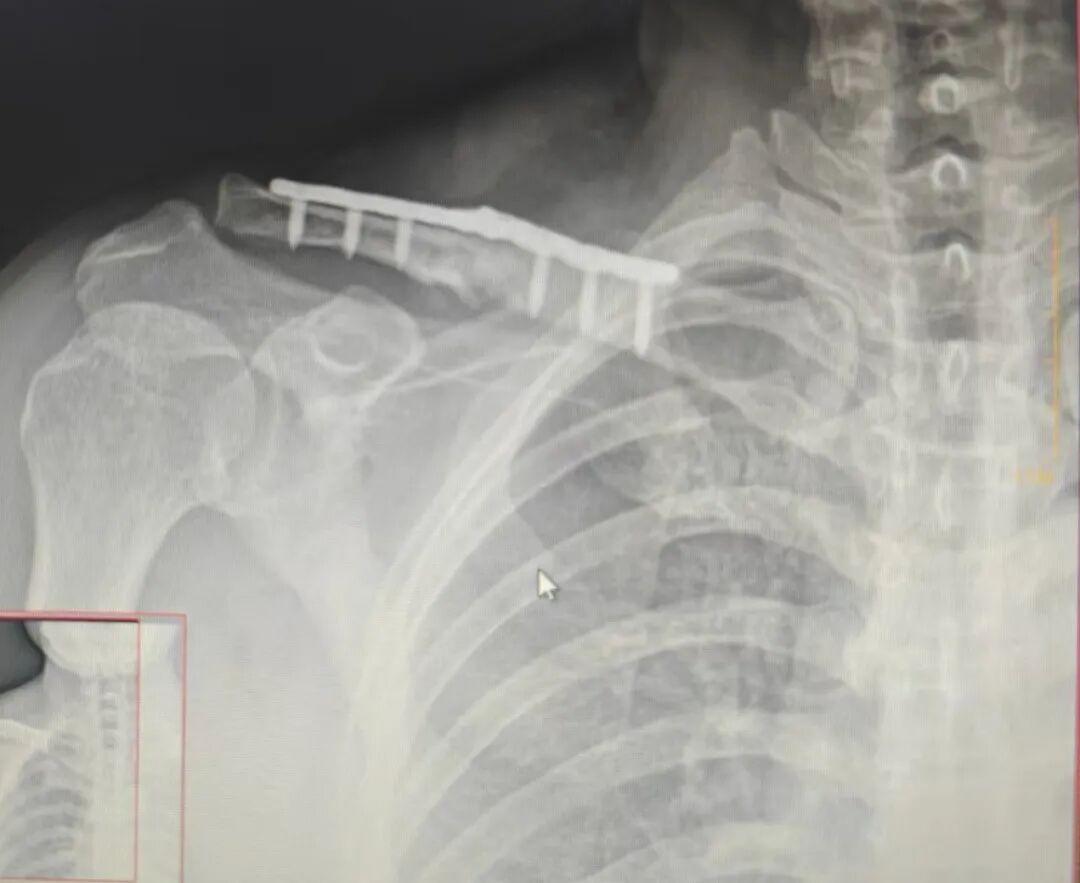

怎么处理?翻修?

取髂骨植骨?前侧加板?

患者强烈恐惧手术

拒绝再手术

怎么办?

有没有一种非手术治疗?

前臂悬吊,保守吧